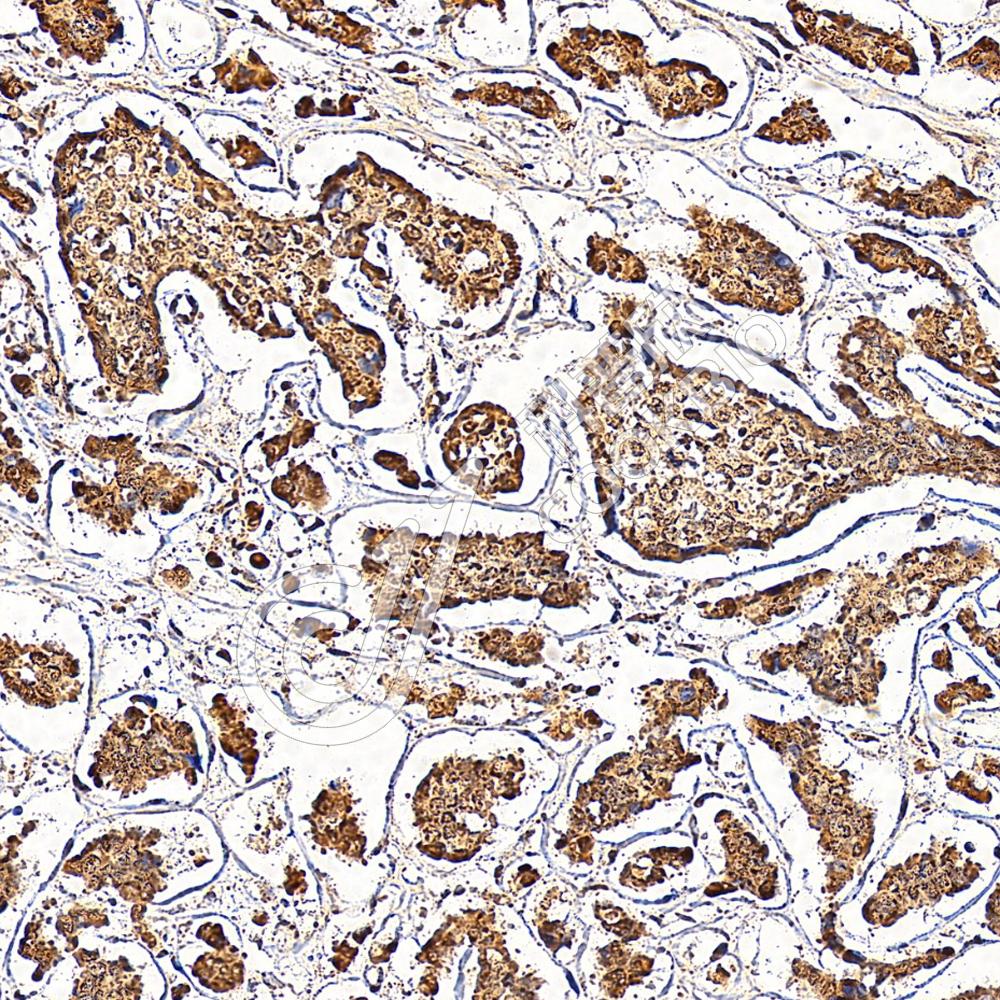

IHC检测TOX蛋白(货号 K1338361).

样品: 小鼠胸腺, 4%多聚甲醛 (货号KSG1101) 固定12-24小时.

抗原修复: Tris-EDTA抗原修复液(pH 9.0) (KSG1203), 98℃, 20分钟.

—抗: 1: 3000稀释, 4℃ 孵育过夜.

二抗: S-vision免疫组化多聚二抗(山羊抗兔),即用型 (货号KB3906), 室温孵育20分钟.